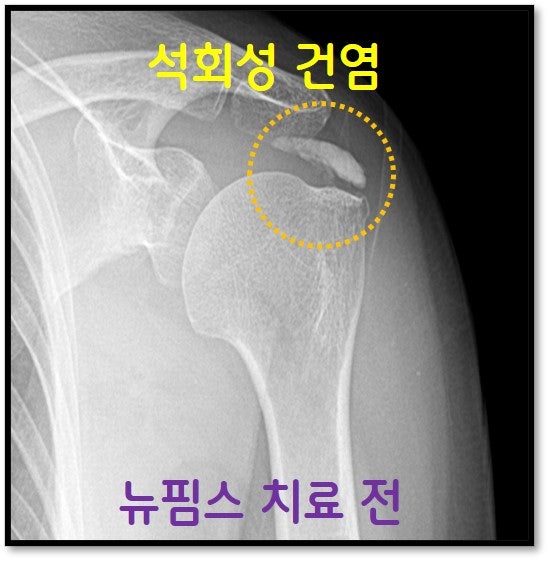

안녕하세요. 정형외과 전문의 이동규 입니다. 오늘은 67세 여자 환자분, 석회성 건염 치료한 사례를 보여드리겠습니다. 역시나 어깨 석회성 건염이 심하게 있어 극심한 통증을 호소 하였습니다. 타병원에서 수술적 치료를 권고 받았으나 수술이 무섭고 다른 방법이 없나 해서 저한테 내원하신 분입니다. 우선 X-ray 를 살펴보겠습니다.

MRI 상 극하근 상부에 커다란 석회가 있는 것이 관찰됩니다.